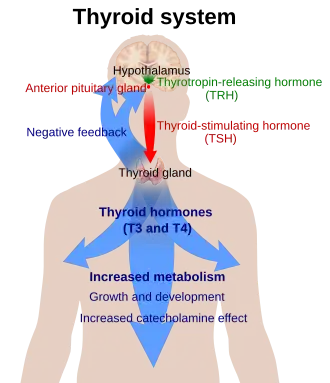

Regulação

A produção de tiroxina e triiodotironina é regulada principalmente pelo hormônio estimulador da tireoide (TSH), liberado pela glândula pituitária anterior. A liberação de TSH, por sua vez, é estimulada pelo hormônio liberador de tireotropina (TRH), liberado de forma pulsátil pelo hipotálamo.[39] Os hormônios da tireoide fornecem feedback negativo para os tireotrópicos TSH e TRH: quando os hormônios da tireoide estão altos, a produção de TSH é suprimida. Este feedback negativo também ocorre quando os níveis de TSH estão altos, fazendo com que a produção de TRH seja suprimida.[40]

O TRH é secretado em uma taxa aumentada em situações como a exposição ao frio, a fim de estimular a termogênese.[41] Além de ser suprimida pela presença de hormônios tireoidianos, a produção de TSH é atenuada pela dopamina, somatostatina e glicocorticóides.[42]